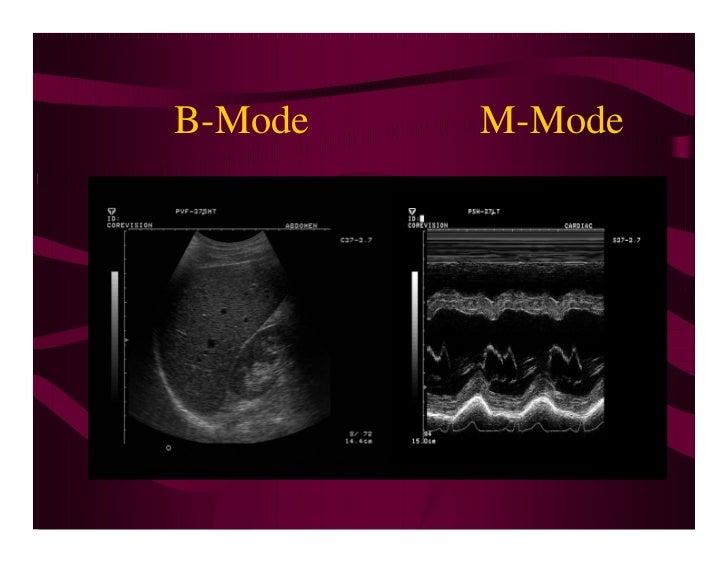

From www.slideshare.net

Basic physics of ultrasound.JH Difference Between B Mode And M Mode Ultrasound Modern ultrasound systems come with many controls & functions. Read about the most commonly available ultrasound modes and how they are used. It is represented by the conversion of ultrasound waves into. In this guide, we’ll explore the fascinating realm of ultrasound modes and how they can enhance your imaging experience. Ultrasound modes, or options when it comes to ultrasound. Difference Between B Mode And M Mode Ultrasound.

From www.slideserve.com

PPT Modes Ultrasound PowerPoint Presentation, free download ID5466126 Difference Between B Mode And M Mode Ultrasound It is represented by the conversion of ultrasound waves into. Read about the most commonly available ultrasound modes and how they are used. Modern ultrasound systems come with many controls & functions. In this guide, we’ll explore the fascinating realm of ultrasound modes and how they can enhance your imaging experience. Ultrasound modes, or options when it comes to ultrasound. Difference Between B Mode And M Mode Ultrasound.